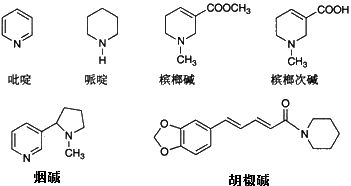

槟榔中含有多种生物碱,它最主要的是槟榔碱和槟榔次碱。

它们如尼古丁里面的烟碱一样会对人体机能产生影响。

几种常见的生物碱,槟榔中包含的生物碱有槟榔碱和槟榔次碱等。

槟榔碱先是刺激内源性促肾上腺皮质激素释放激素的分泌。

之后让人的脑垂体释放更多的促肾上腺皮质激素,从而让肾上腺产生更多的肾上腺皮质激素。

简单来说,就是这些碱进入人体后会让人兴奋并容易上瘾的感觉。